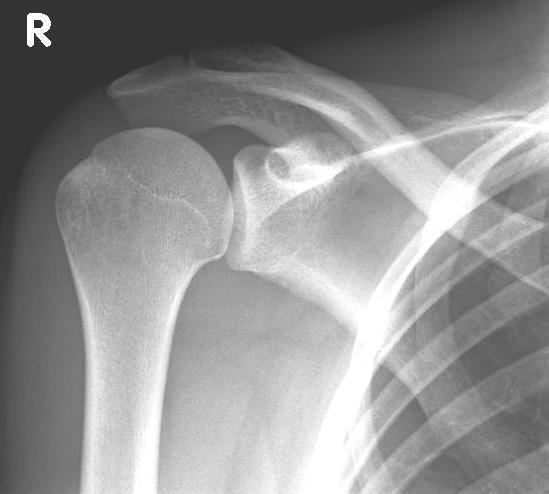

left: X-ray image of an omarthrosis

right: X-ray of a healthy shoulder joint